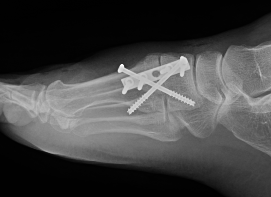

Fixation

- screws / plate / screws + plate